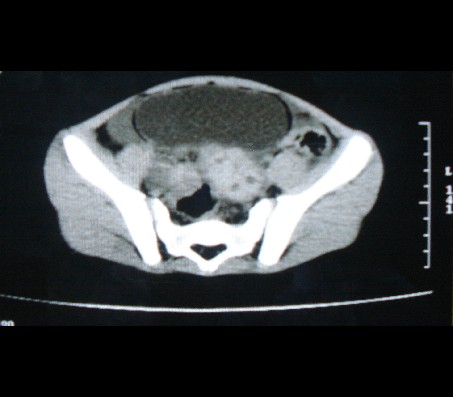

标题: PED0942:女性,8岁,B超提示盆腔病变,请会诊! [打印本页]

标题: PED0942:女性,8岁,B超提示盆腔病变,请会诊!

畸胎瘤

考虑畸胎瘤可能性大!

建议增强进一步检查除外畸胎瘤。